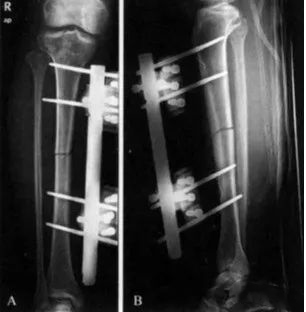

2)置针方法:一般要求固定针应离开骨折端4~5cm左右进针,并确保针尖穿透对侧骨皮质固定。

(穿针外固定进针角度,在连接之前的∠2与骨干纠正之后的∠3,应相等)

通常先以直径较螺纹针细的钻头钻孔,再拧入螺纹针。在首枚固定针旋紧后,置入同一针夹上的另一固定针时应使用导向器,使2枚固定针在固定架上保持平行。若将2枚不平行的固定针强行固定在支架上,可产生异常应力,导致后期骨溶解,固定针容易松动。

在安装连接杆时,杆与皮肤的距离要合适,连接杆离肢体越近,骨折固定越稳定,但过近则不利于引流和针道护理,一般以2cm为宜。对稳定骨折(横行或短斜形骨折),可对骨折做加压固定,可通过微调固定杆的长度进行加压。对不稳定骨折,针组间不能加压,往往需要外固定器的原位固定,骨折端加压可借助有限内固定或附加其他固定针进行靠拢加压。